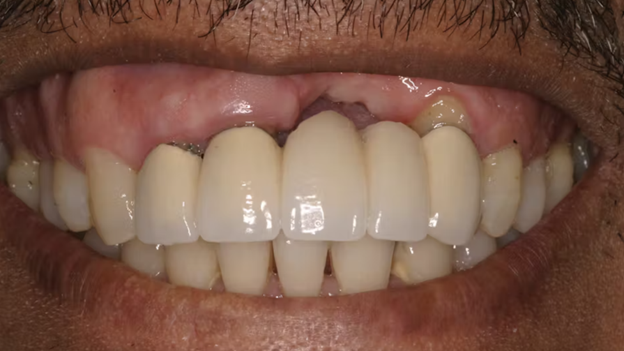

Placing a dental bridge in an area of poor bone volume also creates food traps, whistling and spitting while speaking, and esthetic challenges.

In such cases, grafting preserves tissue volume and protects the intimate contact of the prosthesis and tissue.